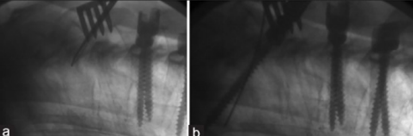

图27 近端置钉和弯棒技术

(1)UIV和UIV-1置钉角度;

(2)UIV螺钉置入时保留2个螺钉螺纹在后方皮质外;

(3)近端棒预弯角度(PRCA)应与固定近端两螺钉的角度一致,以防止棒与上端螺钉之间存在向后的拔出应力。